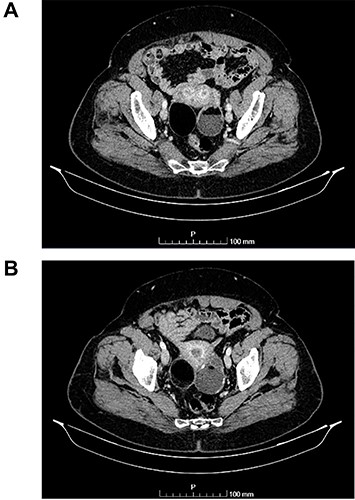

(A and B) Coronal images of CT showing bilateral ovarian lesions.

The authors report the case of an asymptomatic 76-year-old female patient, referred to our Gynaecologic Clinic, due to suspicious adnexal lesions on a pelvic ultrasound (US). Menopause occurred at age 53. She had no history of abnormal uterine haemorrhage. Her menstrual cycles had been regular. She had had three gestations: two late abortions and one normal delivery, after which she breastfed. At our clinic, upon examination, vulva, vagina and cervix had no apparent lesions. The vaginal US revealed a right adnexal avascular cystic lesion of 65 mm, a left adnexal hyperechogenic cystic lesion of 60 mm, a normal sized uterus, a diffusely heterogeneous myometrium, an endometrial thickness of 8 mm and heterogenous intracavitary liquid. Her risk of ovarian malignancy assessment (ROMA) score was 28.1%, for a cut-off of 25.3%. Cancer antigen (CA) 125 and Human epididymis protein 4 (HE4) were 25.9 and 98.2, respectively. Lactate dehydrogenase (LDH), alpha fetoprotein (AFP) and beta human chorionic gonadotropin (bHCG) were normal. She subsequently had a magnetic resonance (MR) done (Fig. 1), which suggested bilateral ovarian teratoma. She also had an upper digestive endoscopy and a hysteroscopy that were normal and a computed tomography (CT) done (Figs 2–4) that showed: in the right adnexal region, a solid well-demarcated tumoural mass of 55 mm, with predominantly fat density, peripherical calcifications and a central hyperdense image (similar to a tooth), suggestive of a teratoma; in the left adnexal region, a predominantly cystic bilobated tumoural mass of 65 mm, with peripherical calcifications and an area of fat density, also suggestive of teratoma; and no additional disease. This case was presented at our Multidisciplinary Tumour Board, where surgery was proposed. Thus, she underwent exploratory laparotomy, peritoneal washing, total hysterectomy and bilateral adnexectomy, which ran uneventfully. Intra-operative frozen section excluded ovarian malignancy. She had an uneventful recovery and was discharged home on the third post-operative day. The pathological report revealed bilateral mature cystic teratoma with representation of the three germinative layers and thyroid parenchymal tissue (struma ovarii) (Fig. 5). Both ovaries were atrophic and had a cavitated lesion covered by respiratory epithelium with hyaline cartilaginous, adipose, smooth muscular and mucosa-associated lymphoid tissues (positivity for CD3 and CD20), seromucinous glands and thyroid follicles (homogenous positivity for thyroglobulin). Thyroid follicles were well differentiated, without features of malignancy. Fallopian tubes were normal. There were also uterine leiomyomas and a mucosal endocervical polyp. She was euthyroid and had a thyroid US done, which was normal. Follow-up at first post-operative month, remaining asymptomatic.